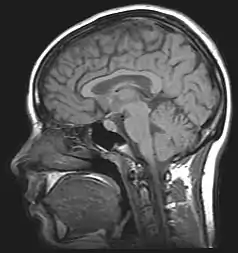

La resonancia magnética hace uso de las propiedades de resonancia aplicando radiofrecuencias a los núcleos atómicos o dipolos entre los campos alineados de la muestra, y permite estudiar la información estructural o química de una muestra. La RM se utiliza también en el campo de la investigación de ordenadores cuánticos. Sus aplicaciones más frecuentes se encuentran ligadas al campo de la medicina, la bioquímica y la química orgánica. Es común denominar "resonancia magnética" al aparato que obtiene imágenes por resonancia magnética (IRM, o MRI por las siglas en inglés de Magnetic Resonance Imaging).[cita requerida]

Aplicación en medicina

La resonancia magnética es una técnica que sirve para diagnosticar enfermedades mediante la obtención de imágenes del cuerpo. A pesar de que no existe efecto nocivo sobre el paciente, no se recomienda la práctica en embarazadas, salvo que su uso sea imprescindible.

La máquina que se utiliza en la resonancia magnética, debido a su dimensión y su tecnología, combina las ventajas de los equipos de alto campo magnético y los equipos abiertos. Así, se consigue una mayor definición y una mayor calidad en la imagen, y el paciente tiene una menor sensación de claustrofobia y además tiene una mayor comodidad. La duración de la prueba no depende de la gravedad de la afección, sino que depende de la región que se vaya a estudiar.[cita requerida]